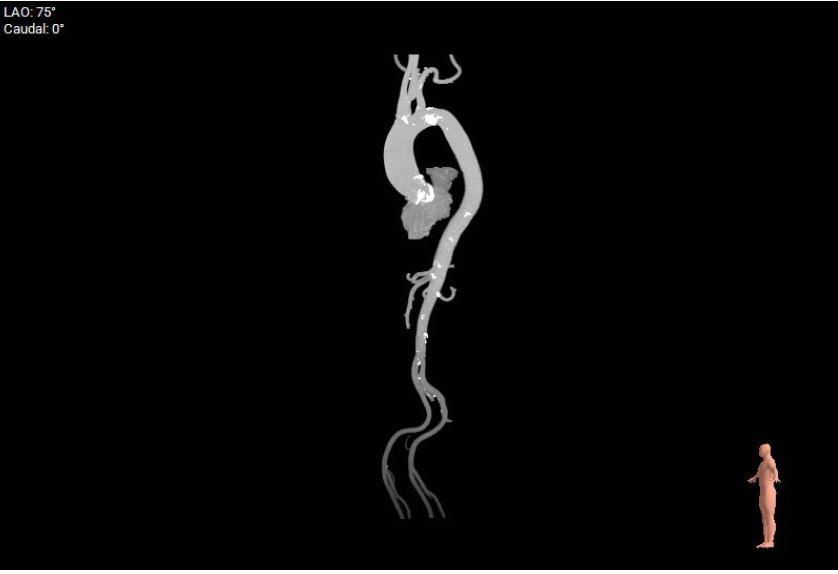

主动脉瓣结构分析:

type 1型主动脉瓣,左右融合,瓣叶增厚,重度钙化,钙化分布于三窦瓣叶。

瓣环周长87.4mm,均径27.8mm;LVOT周长90.6mm,均径28.8mm。

瓣上4/6/8mm预估可推开周长为81.1、79.2、77.5mm。

建议20mm球囊预扩,TAV27瓣膜,备24瓣膜。

极重度钙化,存在瓣周漏可能。

术中DSA影像